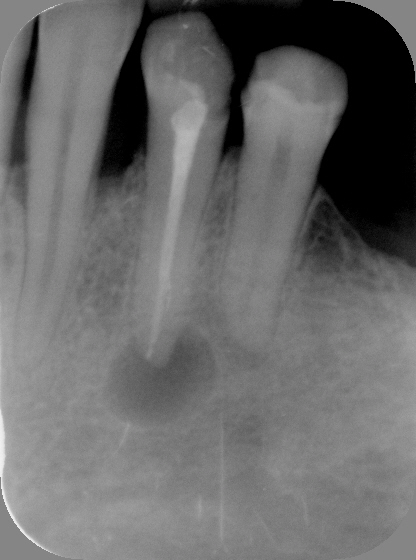

Der Zahnfilm ist eine kleine Röntgenaufnahme, die nur einen begrenzten Bereich des Kiefers zeigt – in der Regel ein bis drei Zähne mit den umgebenden Strukturen. Der Röntgenfilm oder digitale Sensor (etwa 2 × 3 cm oder 3 × 4 cm) wird dabei direkt in den Mund gelegt und vom Patienten mit dem Finger oder einer Halterung in Position gehalten.

Die Aufnahme dauert nur Sekundenbruchteile. Da der Sensor nah am Zahn liegt und der Röntgenstrahl gezielt auf einen kleinen Bereich gerichtet ist, liefert der Zahnfilm eine deutlich höhere Detailschärfe als das OPG (Orthopantomogramm). Feine Strukturen wie beginnende Karies, Wurzelkanäle oder der exakte Verlauf des Knochens an einzelnen Zähnen lassen sich präziser beurteilen.

Implantate, Karies, Wurzelentzündungen: im Zahnfilm sicher zu beurteilen

Typische Einsatzgebiete sind die Kariesdiagnostik (besonders die sogenannten Bissflügelaufnahmen für die Zahnzwischenräume),

Die Beurteilung von Wurzelkanalfüllungen, der Verdacht auf Wurzelspitzenentzündungen, die Kontrolle nach Zahnentfernungen oder Implantationen sowie die genaue Darstellung des Knochenabbaus bei Parodontitis. Ein vollständiger Röntgenstatus aus 10 bis 14 Zahnfilmen zeigt das gesamte Gebiss in hoher Auflösung, wird aber wegen des höheren Aufwands nicht routinemäßig angefertigt.